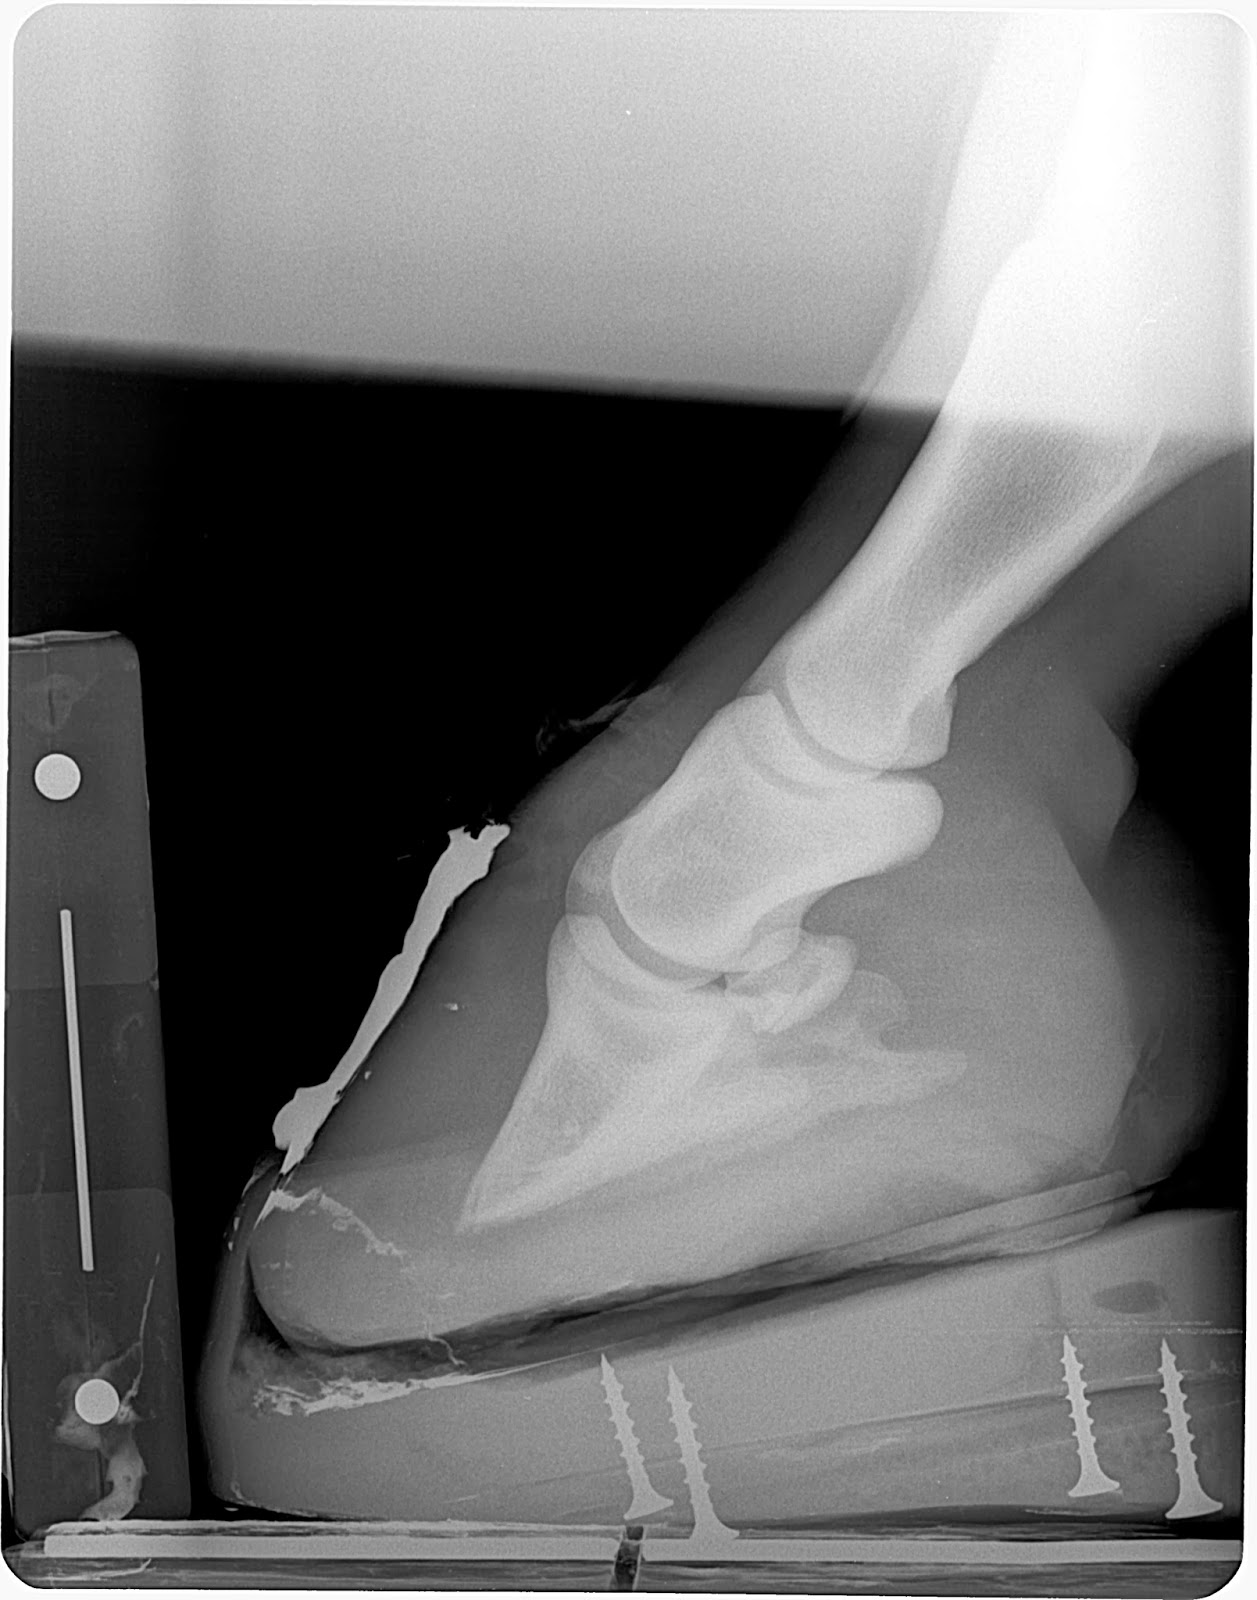

Figure 6 long toe low heel/neg pa hoof

versus a grade 3 club

Figure 6 is comparing measurements in two different adult horses. One with severe negative palmar angle and the

other a grade 3 club. Note the

difference in bone angle, palmar angle, tendon surface angle and the static toe

lever. These differences must be

considered and exemplifies the reason that all hooves can't be shod the exact

same way and expect it to fit all the different foot types. It is similar to asking us all to wear the

same size pants even though we all have our unique characteristics.